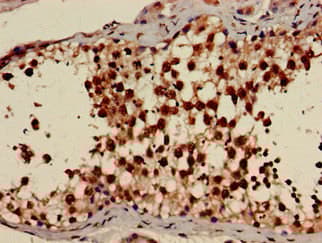

Rabbit Polyclonal AMPK gamma 1 antibody. Suitable for WB, IHC-P, ICC/IF and reacts with Rat, Human samples. Immunogen corresponding to Recombinant Full Length Protein corresponding to Human 5'-AMP-activated protein kinase subunit gamma-1.

Applications ICC/IF, IHC-P, WB

Species Reactivity Human, Rat